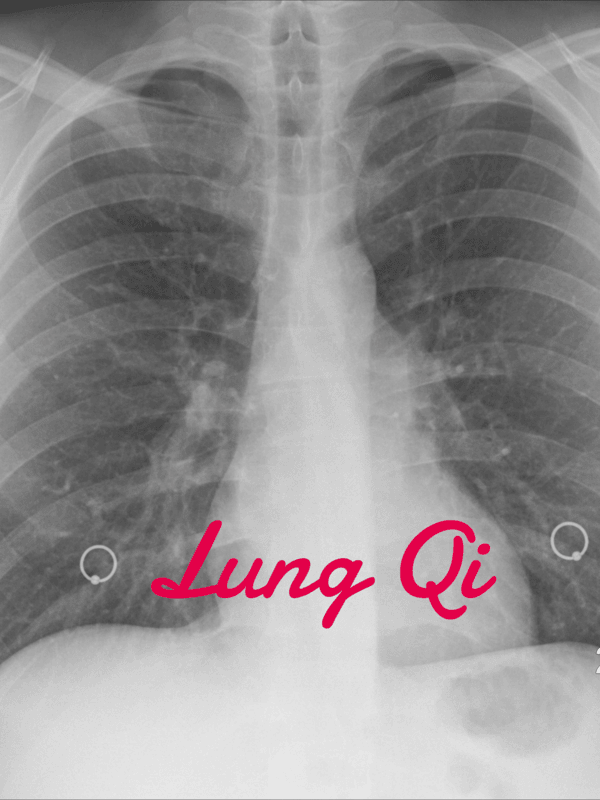

Facial diagnosis for the Lungs

The Lung Qi is seen in the cheek area and in the quality of the skin, if there are many wrinkles the lungs are not healthy.